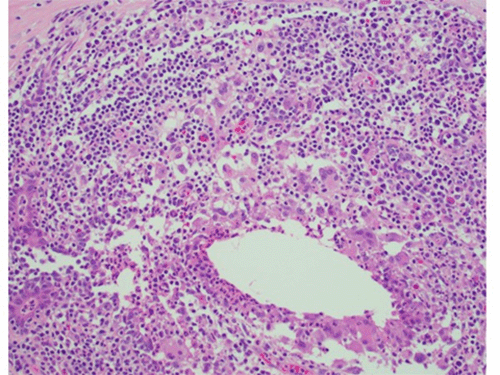

An aspiration of the abscess was performed, obtaining 8 ml of thick purulent fluid. The patient was then admitted to the hospital for two days of IV antibiotics. The aspirate culture grew normal skin flora, and the patient underwent a surgical incision and drainage of her right breast abscess. Purulent fluid was observed at the time of operation, and a firm granulomatous mass was appreciated. Cultures from the operation again grew out normal skin flora, fungal and acid-fast bacilli were negative, and histopathology showed fat necrosis with histiocytic granulomatous inflammation. (Figure 2) No special stains were done, and the patient received IV clindamycin while in the hospital.

Figure 2. Breast Pathology, Granulomatous Mastitis. Published With Permission

Right breast histopathology showing granulomatous inflammation with giant cells, histiocytes, and admixed lymphocytes; 20x magnification.